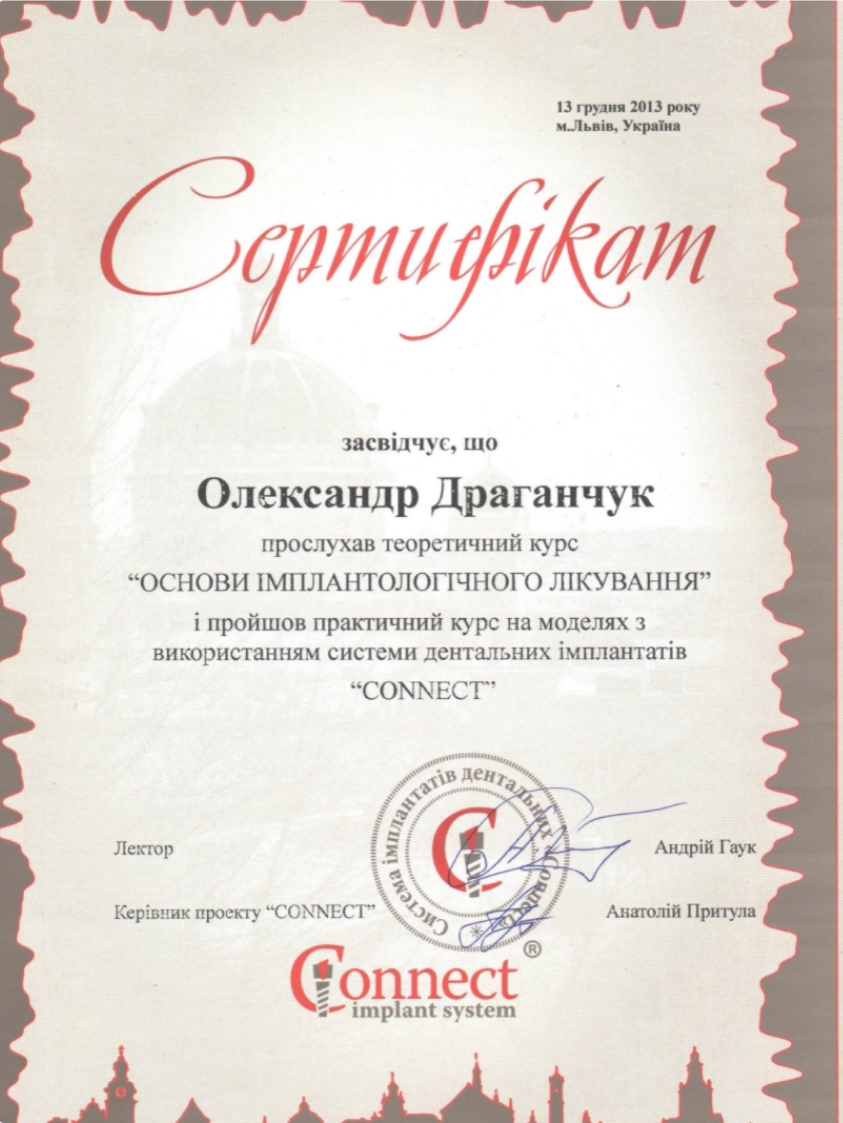

Ми пропонуємо тобі усю стоматологію в одній клініці. У нас ти отримаєш кваліфіковану стоматологічну допомогу: лікування і пломбування зубів та кореневих каналів, послуги з протезування, імплантації та стоматологічної хірургії. Космічна стоматологія Драганчука, це досвідчені фахівці, які навчались та стажувались в Берліні, Парижі, Вільнюсі та Будапешті, найсучасніші та найінноваційніші матеріали та обладнання.